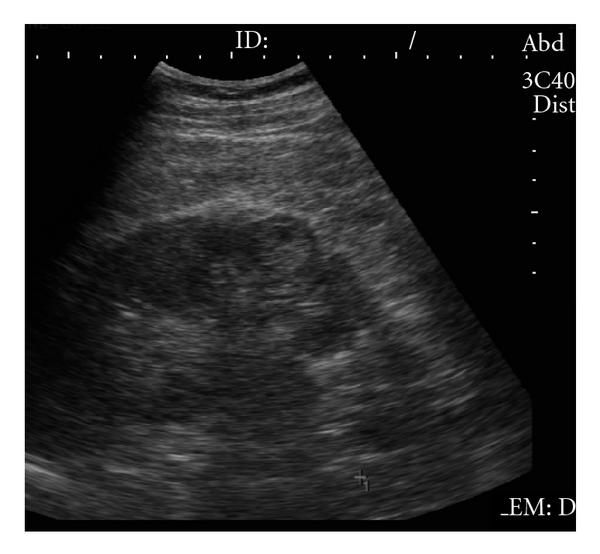

In the general population, renal cysts are the most common space-occupying lesions in the kidney. With this technique, 80% of detected renal masses are characterized as simple cysts [9] thus ending their diagnostic evaluation. The remaining 20% of renal masses require further study with CT or MR imaging [10]. Any mass detected that does not meet the strict sonographic criteria for a simple cyst should be further evaluated with CT or MR imaging of the kidneys. However, one or two thin septations may also be visible sonographically in simple renal cysts [11]. Because these findings are diagnostic, no further imaging or followup is needed in the evaluation of these lesions. However, other atypical features sonographically detected calcifications; more than two septations, septal thickening or nodularity, and the presence of solid components indicate that sonography alone will not be adequate for complete evaluation of these renal masses (see Figure 2). The addition of Doppler sonography, color Doppler sonography, power Doppler sonography [12, 13], and sonographic contrast agents may further improve the detection and characterization of renal masses. However, none of these techniques preclude the need for CT or MR imaging of renal masses that do not meet the sonographic criteria for diagnosis of a simple cyst.

In the study of solid renal masses, the role for US has been mainly centred on the differentiation of RCC and AML, which are the most common malignant and benign solid renal tumors, respectively [14–17]. When a solid mass is diagnosed, RCC or AML should be initially considered because of the high frequency of their occurrence. At US, most AML lesions are markedly hyperechoic relative to renal parenchyma. They may appear less echogenic depending on the relative proportion of fat, smooth muscle, vascular components, and haemorrhage in the lesion [18, 19]. RCC displays a broad range of echogenicities. Although often thought of as hypoechoic or isoechoic, recent studies have shown that most RCC are hyperechoic relative to renal parenchyma and that up to 12% simulate AML [14–17]. Forman et al. [14] have shown that one third of small RCC are as echogenic as a “classical” AML. An echotexture equal to that of renal sinus fat seen in a small renal mass is, therefore, no longer considered adequate to exclude the diagnosis of malignancy (see Figure 3).

Other ultrasound signs have been used to differentiate between hyperechoic RCC and AMLs. The presence of an anechoic rim and/or an intratumoral cyst is only seen in RCC (see Figure 4). The presence of acoustic shadow is specific of AML. However, the detectability of these findings varies [15, 16], their diagnostic value has not been established, and the presence of these features is not sufficient to differentiate RCC from the other solid renal masses that are incidentally detected on gray-scale US. On the power Doppler US, the analysis of the vascular distribution has not increased the diagnostic accuracy for small renal tumors [12]. Contrast-enhanced Doppler US can increase the detection of intratumoral vascularity compared to color/power Doppler US [20]. However, their signal intensity has not been found to be sufficiently intense for tumor characterization. Recently, the development of contrast-enhanced harmonic US imaging has provided a better assessment of the diagnostic accuracy of RCC as compared with gray-scale US by allowing better visualization of the intratumoral anechoic areas and the pseudocapsule than can the gray-scale US [21], but there still exists an overlapping of signs of RCC and the other solid renal masses, making it necessary to use CT or MR imaging in the study of small renal masses.